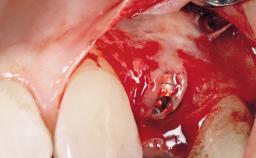

Immediate Flapless Placement of an Implant in a Maxillary Right Lateral Incisor Site

This 43-year-old male patient, a non-smoker, came to our practice because of a fracture of tooth 12 caused by a bicycle accident. Due to the combined para- and infrabony crown and root fracture, tooth extraction, and subsequent implant placement were suggested to the patient as the therapy of choice. The patient had high esthetic expectations with regard to the treatment outcome and asked for an immediate fixed provisional restoration. His individual esthetic risk profile summed up to a medium esthetic risk.

Placement Protocol Immediate implant placement

Tooth Site Maxillary incisor or canine

Socket Integrity Sufficient, with intact bone walls

Bone Volume Sufficient, with intact walls